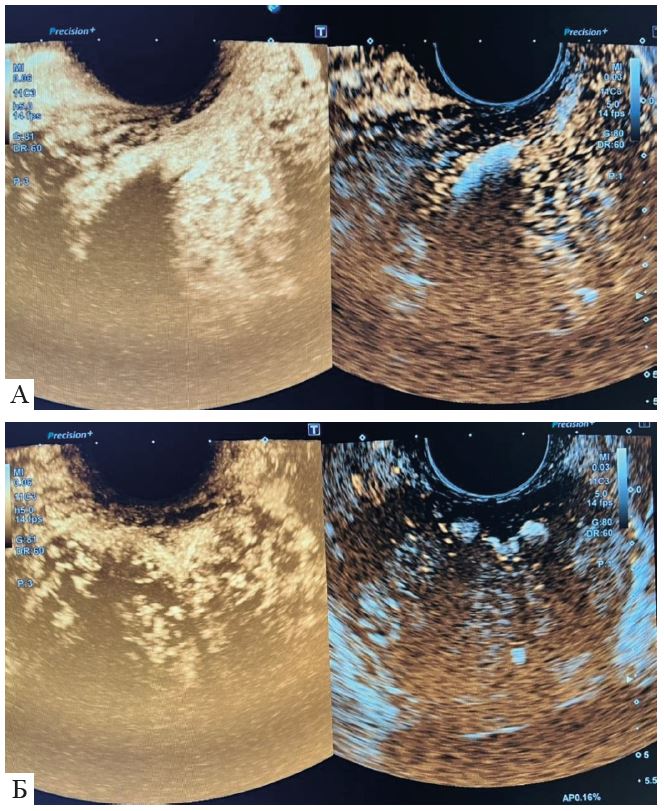

Тимчасові та просторові характеристики контрастування паренхіми дозволяють отримати повну характеристику осередкових уражень ПЗ. Найважливішими критеріями оцінки є:

- вираженість васкуляризації (гіпер-, ізо-або гіпоехогенне утворення порівняно з нормальною паренхімою);

- судинна архітектоніка (тобто тип сходинки чи колеса, тип кошика, периферійно-вузловий тип);

- динаміка в часі (швидка/повільна, рання/пізня).

Значення ПСА вище вказаних значень до 10 нг/мл прийнято позначати «сірою зоною», коли важко визначити показання до проведення біопсії ПЗ. Значення ПСА вище 10 нг/мл є основою проведення біопсії ПЗ. Хворому була виконана трансректальна поліфокальна біопсія ПЗ під мультипараметричною (мп) ультразвуковою навігацією та ехоконтрастуванням Соновью (рис. 1 - 5).

Патогістологічний висновок: ацинарна аденокарцинома (Gleason Score 3 + 4 = 7) лівої частки ПЗ без лімфоваскулярної та периневральної інвазії (рис. 1-6). На закінчення відзначимо найактуальніше на тему нашої публікації. Точність діагностики доброякісної гіперплазії ПЗ за допомогою УЗО з ехоконтрастуванням склала 95,6%, а чутливість та специфічність – 95,0% та 96,7% відповідно[4].

Рис. 3. Ехоконтрастування: зліва з використанням програми для контрастів; справа − В-режим; А-сагітальне зображення; Б − фронтальне зображення.